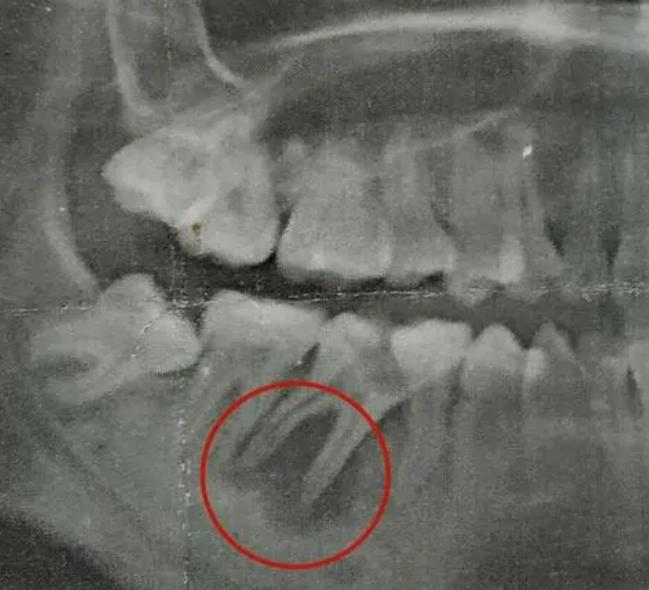

如果牙髓已经坏死的话,也是需要及时进行治疗。治疗方案是根据牙髓坏死程度:

- 如果牙根长度足够,可以将坏死的牙髓清理消杀后进行打桩治疗,保留住原本的牙根。

- 如果牙根已经被吸收,那么这个残根就要及时拔除,然后进行缺牙修复治疗。